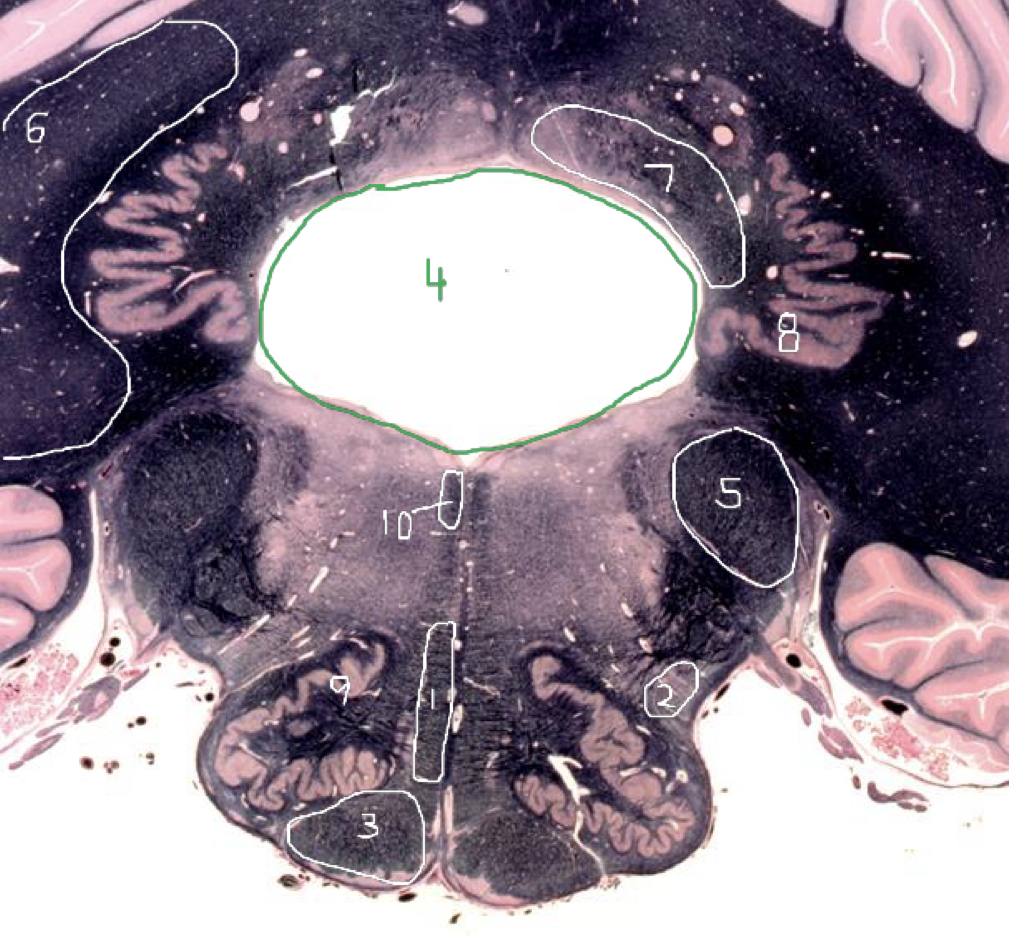

1

Medial Lemniscus - Caudal Midbrain

2

Spinothalamic Tract - Caudal Midbrain

3

CST - Caudal Midbrain

4

Cerebral Aqueduct - Caudal Midbrain

5

Superior Cerebellar Peduncle (Decussation) - Caudal Midbrain

6

Inferior Colliculus - Caudal Midbrain

7

Trochlear Nucleus (CN IV) - Caudal Midbrain

8

Medial Longitudinal Fasciculus (MLF) - Caudal Midbrain